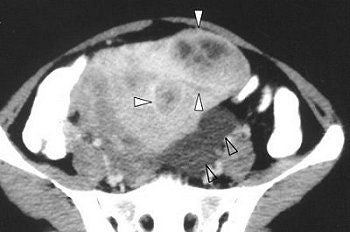

The CT exam with contrast showed heterogeneous enhancement of the solid components and septations of the corneal complex cystic lesions. T1- and T2-weighted MR scans showed isointense septations of the left cornual cystic lesions and small myometrial nodules. These same findings were hyperintense on gadolinium-enhanced MR.

| Axial contrast-enhanced CT shows heterogeneous enhancement of solid components of myometrial nodules (solid arrowheads) and left adnexal peritoneal inclusion cyst (open arrowheads). |